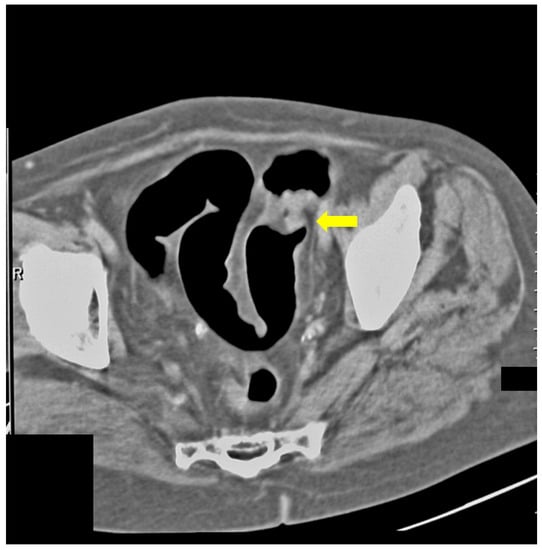

The following case was an 80-year-old patient who underwent FCS, on which there was evidence of compression of the colon. CT colonography showed tumor formation with irregular outlines and inhomogeneous density arising from the caecum (Figure 6).

Figure 6.

CT colonography-axial slice; 80-year-old patient with incomplete FCS obturation from extraluminal origin was suspected (yellow arrow). After CT colonography, cancer of the cecal valve was found.